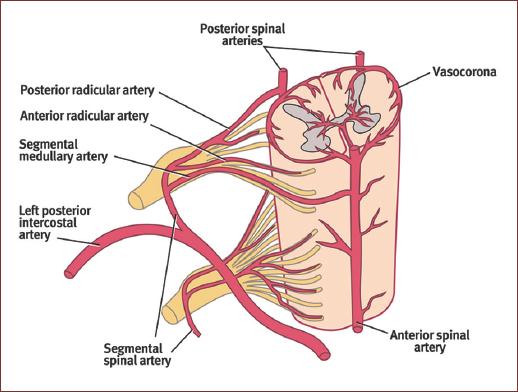

Superficially, the anterior two-thirds of the spinal cord is supplied by the anterior spinal artery (ASA), which originates from a medial branch of the intracranial vertebral artery on both sides, which join together in the midcervical spine (C2-C4) and travel along the anterior medial fissure (Fig. 1). The dominant contributors to this artery are six to eight segmental radiculomedullary arteries, which typically include:

This posterior system is also referred to as the dorsolateral pial supply or centripetal system (Fig. 1). This network gives off radial arteries that circumferentially run along the spinal cord, reaching anastomosis with the ventral system (forming a pial plexus called the vasocorona), and giving off axially oriented perforating branches into the white matter5.

Imaging is an essential component in the diagnosis, management, and follow-up of patients with AVMs in the brain and spine. A wide variety of imaging modalities are available for its use, such as computed tomography (with its permutations: non-contrast, contrast enhanced, angiography perfusion, and myelography (Fig. 1) and magnetic resonance imaging (with its permutations: non-contrast, contrast enhanced, angiography, and myelography (Fig. 2). Although advances in this noninvasive imaging, digital subtraction angiography continues to be the gold standard for diagnosing and characterizing the detailed anatomic localization, arteriovenous transit, and venous drainage patterns of sAVMs29,33,38.